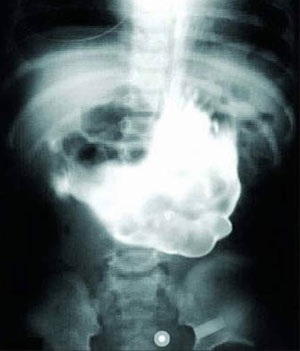

Một cô gái ở thành phố Phật Sơn, thuộc tỉnh Quảng Đông (Trung Quốc) đã nuốt hơn 20 hòn sỏi trong một giây xúc động sau khi cãi nhau với bạn trai. Lúc đầu, cô nghĩ rằng những viên sỏi sẽ ra khỏi cơ thể, nhưng không may nó vẫn ở trong dạ dày.

Vấn đề tồi tệ hơn khi những viên sỏi làm cho cô bị đau và cảm giác không thoải mái. Sau khi chụp X quang ở bệnh viện, các bác sĩ khuyên cô nên phải phẫu thuật để lấy những viên sỏi ra khỏi cơ thể. Sốc và bối rối, cô gái tìm kiếm sự giúp đỡ của mọi người trên mạng. Theo cảnh báo của bác sĩ, cô gái cần phải lấy những hòn sỏi ra khỏi dạ dày càng sớm càng tốt.

Phim chụp X quang cho thấy những hòn sỏi khiến dạ dày cô gái trĩu xuống.